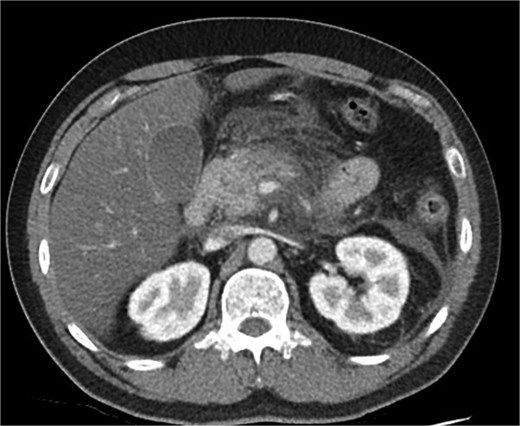

A 39-year-old male presented with one week of worsening epigastric pain radiating to the back, with vomiting, jaundice, and dark urine. His past medical history included depression and alcohol-related liver disease without cirrhosis. On admission he was afebrile, had a soft abdomen with epigastric tenderness worse on palpation, tachycardic, and normotensive. Initial investigations showed a lipase of 2600 U/L, C-reactive protein 238 mg/L, lactate 3.4 mmol/L, and bilirubin 100 μmol/L (Table 1). Abdomen and pelvic computer tomography (CT) demonstrated body and tail pancreatitis, fat stranding, portal vein thrombus, and early necrosis signs, with no choledocholithiasis (Figs 1–3).

Axial CT image demonstrating body and tail pancreatitis with fat stranding.